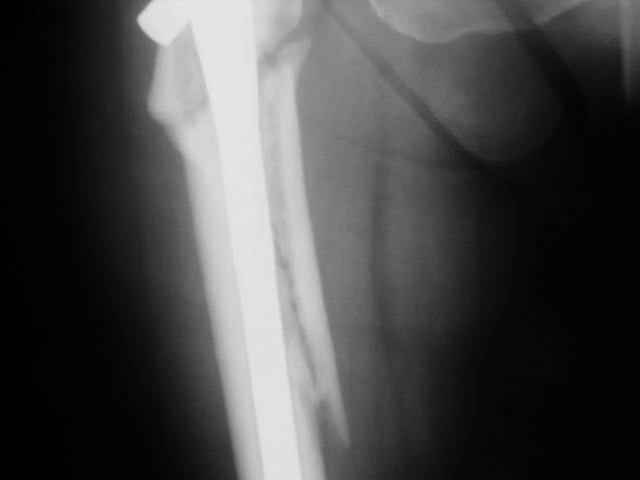

proximal femoral nonunion |

Advice on this case would be appreciated. 59 year old female normal body weight and nonsmoker.

Now 11 months out from initial fixation. No clinical evidence of infection. Closed fracture initially. CT confirms minimal bridging bone. Weightbearing pain in proximal thigh. My initial thought was onlay autogenous bone graft with BMP supplementation and leaving fixation as is. Any benefit to revision fixation and if so what implant? Her ROM and length are symmetric. Thanks.